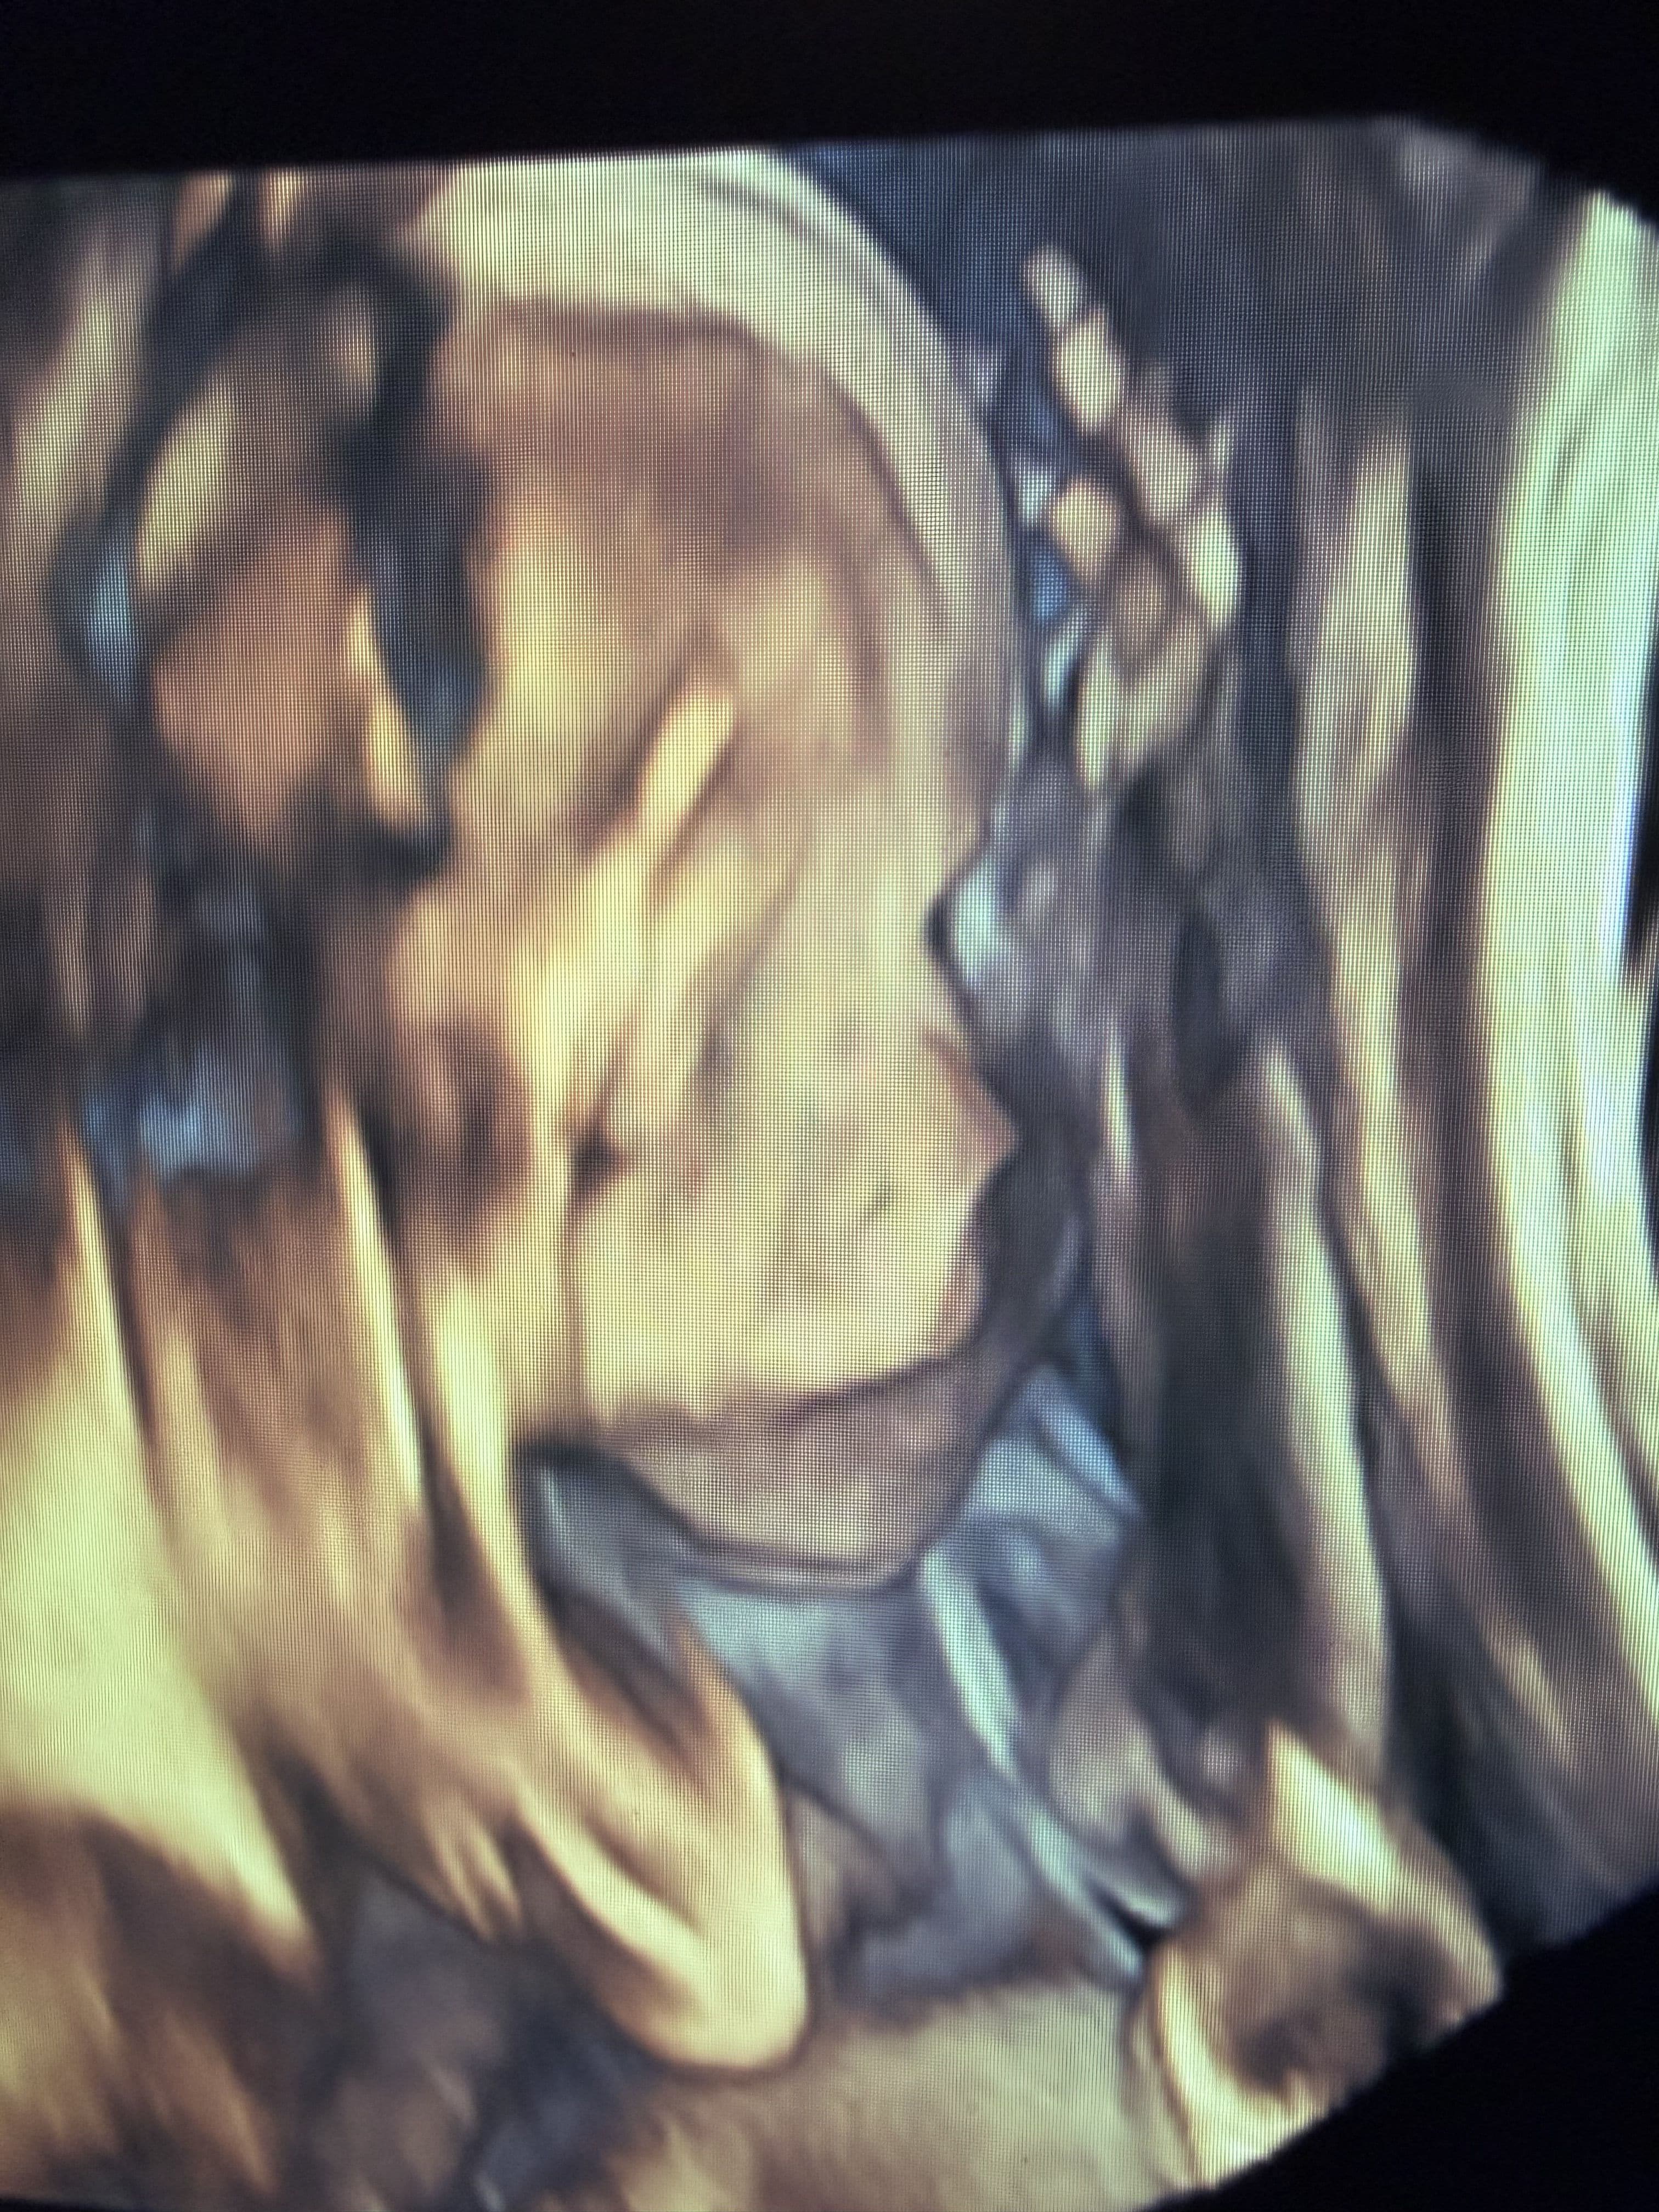

4D Ultrasound